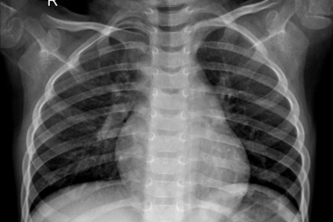

We want to optimise triaging systems and compliment already in place healthcare pathways.